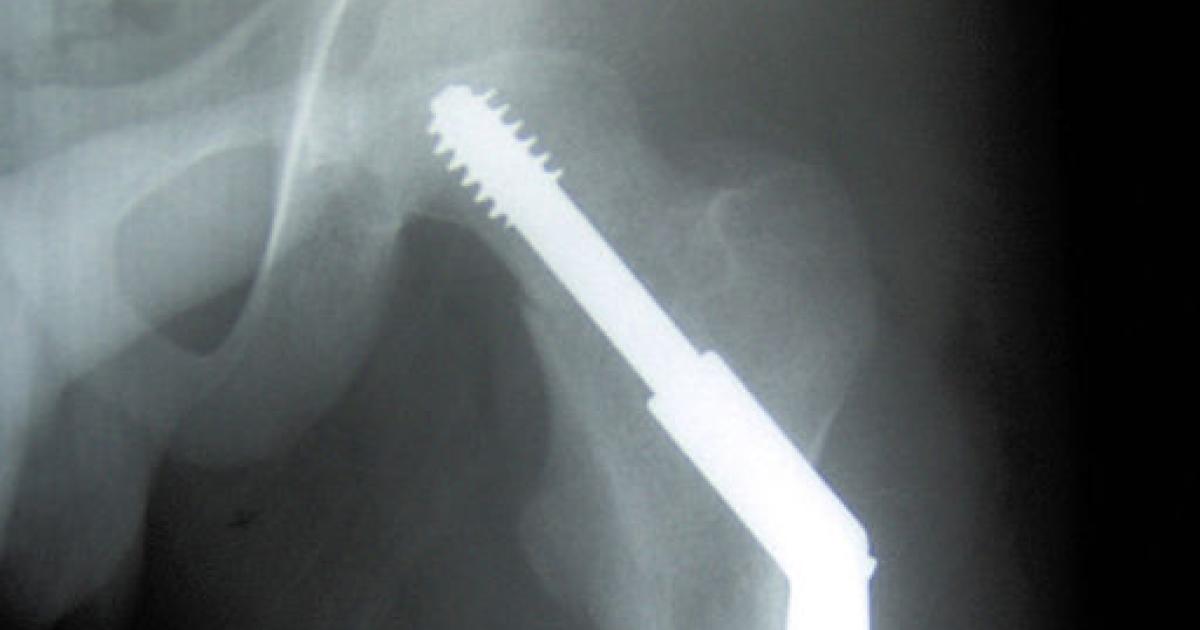

Why do our bones break? In general, for one of two reasons. First, and least likely, pathologic fractures – breaks in the bone due to an underlying focal disease in the bone itself, usually metastatic cancer. Vitamin D and Calcium are not prescribed and do not prevent pathologic fractures. The other, more common cause of bone fractures is trauma, and by that, I mean falling. And falling may be made worse if the bones themselves are weaker, with less calcium, when the patient has osteoporosis. That is why it is essential to understand that the two groups at greatest risk for these fractures, people who fall and people with osteoporosis were not considered. By excluding individuals living in residencies, the authors eliminated the majority of people with ambulatory problems, the ones that fall the most. At the same time, osteoporosis, the decreasing density of the bone, occurs with age and will be greater in this population. The data concerning Calcium and Vitamin D supplements are less clear for these groups.